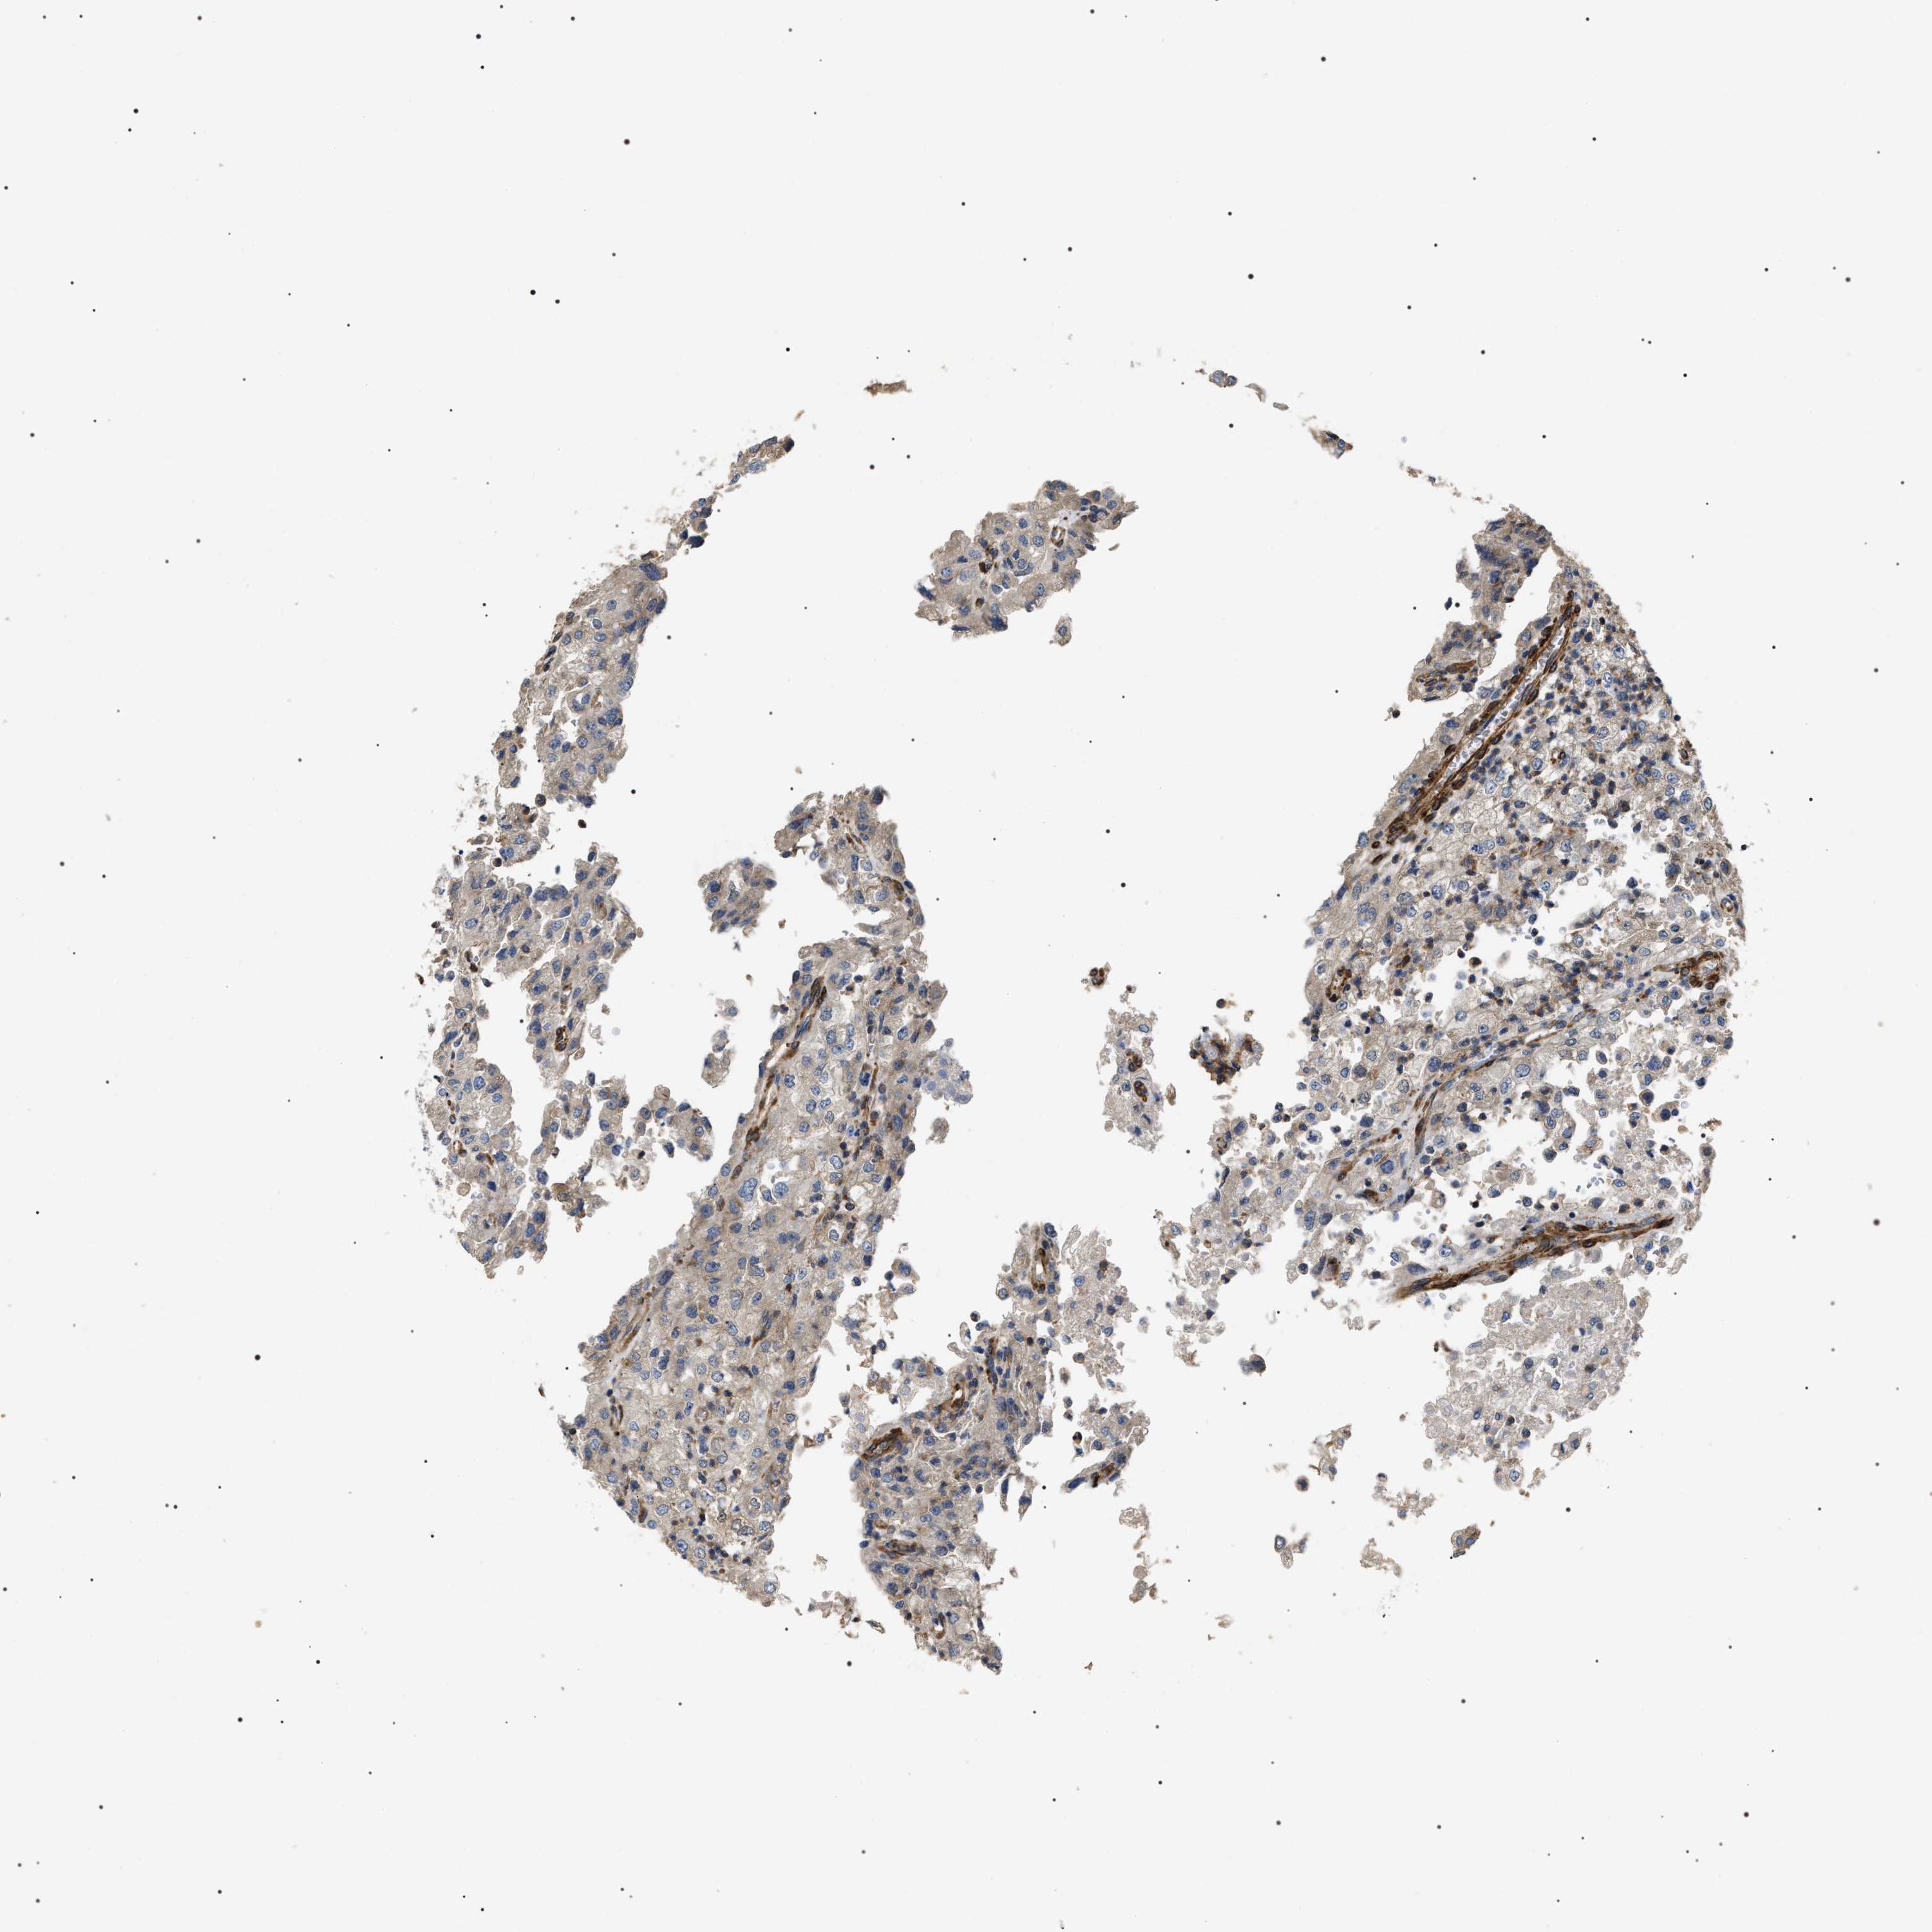

KIDNEY RENAL PAPILLARY CELL CARCINOMA (TCGA) - Interactive survival scatter ploti

The Survival Scatter plot shows the clinical status (i.e. dead or alive) for all individuals in the patient cohort, based on the same data that underlies the corresponding Kaplan-Meier plots. Patients that are alive at last time for follow-up are shown in blue and patients who have died during the study are shown in red.

The x-axis shows the expression levels (FPKM) of the investigated gene in the tumor tissue at the time of diagnosis. The y-axis shows the follow-up time after diagnosis (years). Both axes are complimented with kernel density curves demonstrating the data density over the axes. The top density plot shows the expression levels (FPKM) distribution among dead (red) and alive patients (blue). The right density plot shows the data density of the survived years of dead patients with high and low expression levels respectively, stratified using the cutoff indicated by the vertical dashed line through the Survival Scatter plot. This cutoff is automatically defined based on the FPKM cutoff that minimizes the p-score. The cutoff can be changed by dragging the vertical line or by entering a cutoff value in the square labeled "Current cut-off".

Under the Survival Scatter plot the p-score landscape (black curve; left axis) is shown together with dead median separation (red curve; right axis). Dead median separation is the difference in median mRNA expression between patients who have died with high and low expression, respectively. It is calculated as follows: median FPKM expression of dead patients with high expression - median FPKM expression of dead patients with low expression. This is intended to aid the user in visually exploring custom cutoffs and the associated p-scores and dead median separation.

Individual patient data is displayed and can be filtered by clicking on one or more of the category buttons on the top of the page. Categories describing expression level and patient information include: high, low, alive, dead, female, male and tumor stages. The scale of the x-axis can be toggled between linear and log-scale by clicking on the "x log" button. Mouse-over function shows TCGA ID, patient information and mRNA expression (FPKM) for each patient.

& Survival analysisi

Kaplan-Meier plots summarize results from analysis of correlation between mRNA expression level and patient survival. Patients were divided based on level of expression into one of the two groups "low" (under cut off) or "high" (over cut off). X-axis shows time for survival (years) and y-axis shows the probability of survival, where 1.0 corresponds to 100 percent.

ZC3HAV1L is not prognostic in Kidney Renal Papillary Cell Carcinoma (TCGA)